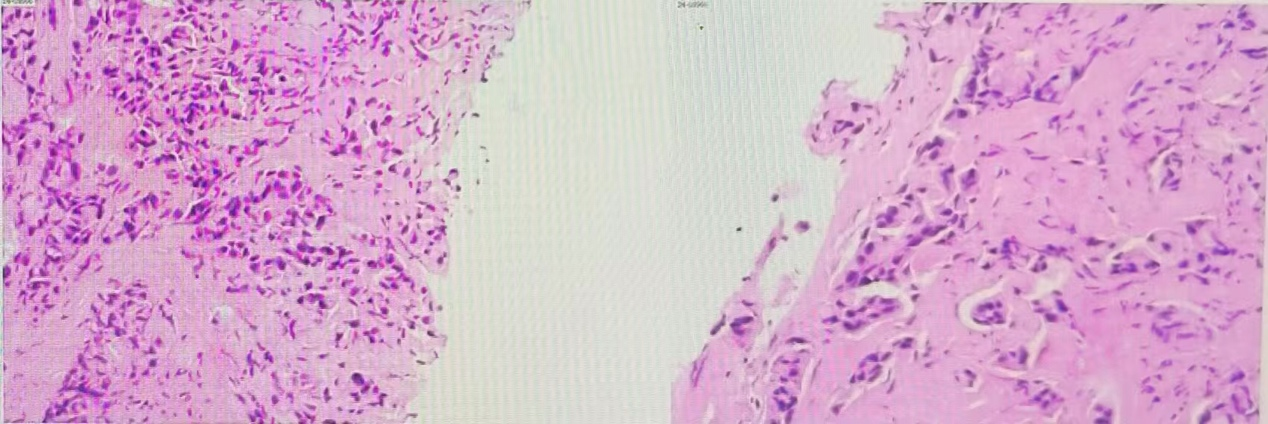

乳腺彩超(2024-7-25):

图 乳腺彩超(2024-7-25)

(左):左乳11点结节:1.27*0.65cm;(右):左侧腋窝淋巴结:2.7cm*1.3cm

右侧胸壁结节:较大者约1.22*0.30cm。

左乳11点结节:大小约1.27*0.65cm。

右侧腋下可及低回声区,范围约1.96*0.62cm。

左侧腋窝淋巴结:较大者约2.7*1.3cm。

乳腺彩超(2024-9-2):

图 乳腺彩超(2024-9-2)

(左):左乳11点结节:1.21*0.59cm;(右):左乳11点结节:1.21*0.59cm

右侧胸壁结节:较大者约1.01*0.35cm。

左乳11点结节: 大小约1.21*0.59cm。

右侧腋下可及低回声区,范围约2.01*0.54cm。

左侧腋窝淋巴结: 较大者约1.8*1.0cm。

乳腺彩超(2024-12-4):

图 乳腺彩超(2024-12-4)

左乳11点结节:0.85*0.45cm

右侧胸壁结节:较大者约0.98*0.25cm。

左乳11点结节: 大小约0.85*0.45cm。

右侧腋下可及低回声区,范围约2.2*0.5cm。

左侧腋窝淋巴结: 较大者约1.4*0.5cm。

乳腺彩超评估肿物变化:

图 乳腺彩超评估肿物变化,见进行性缩小